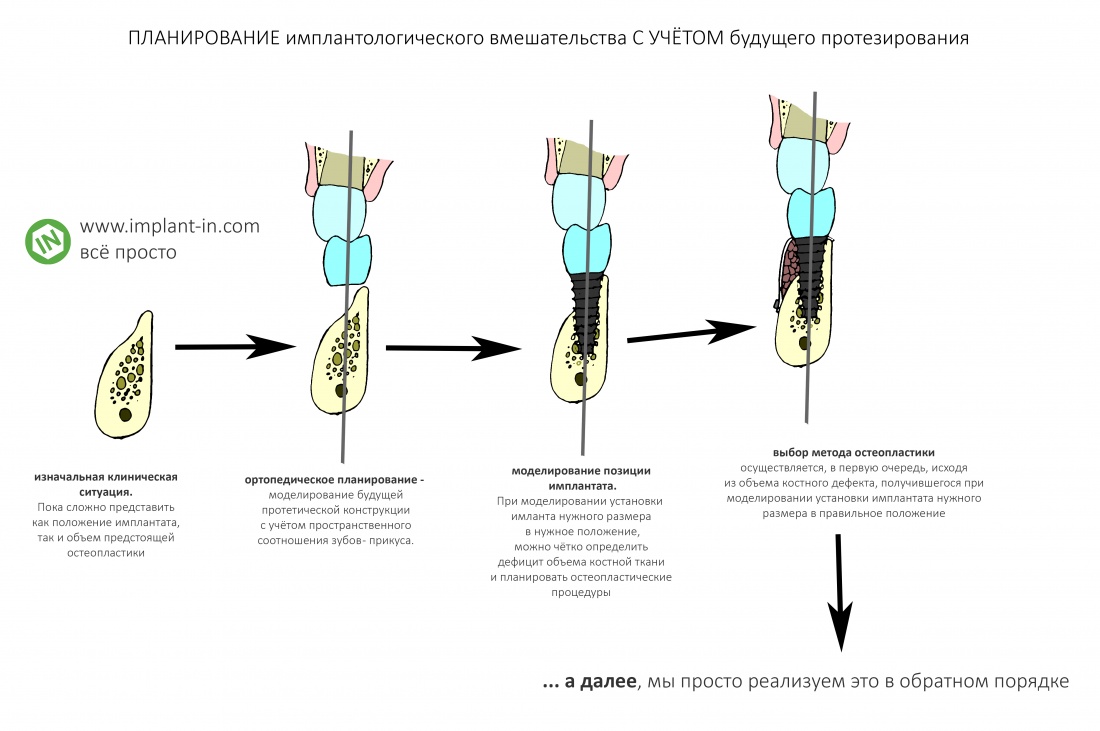

Если вы прочитали всё написанное выше, я думаю, что с имплантологическим анализом клинической ситуации вообще не должно возникнуть никаких проблем. Её можно свести к одной простой фразе:

— мы изучаем возможность установки имплантата нужного размера в нужное, с точки зрения предстоящего протезирования, положение. И, если таковая возможность отсутствует, мы рассматриваем варианты её создания.

Иначе говоря, стоматолога-ортопеда, проектирующего зубной протез с опорой на импланты, совершенно не должны волновать ни объемы костной ткани, ни состояние слизистой — ему важно лишь, чтобы имплантат нужного размера находился в нужном месте. А вот если там вдруг не хватает кости, если слизистая оболочка какая-то не такая — то это уже забота имплантолога, у которого в арсенале есть методики остеопластики («наращивания кости«) и мукогингивопластики («восстановления десны»).